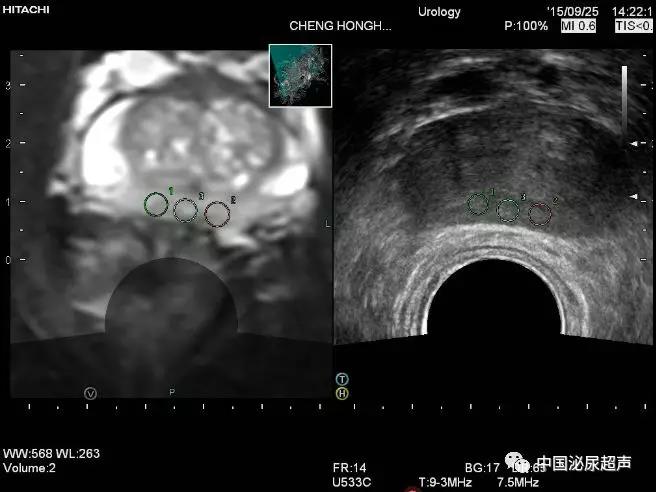

該研究的患者人群為首次進行前列腺活檢的男性。對有MRI可見損傷的患者隊列(定義為前列腺成像報告和數(shù)據(jù)系統(tǒng)第2版分數(shù)?≥?3),使用三種方法進行活檢,包括系統(tǒng)性活檢,認知融合MRI損傷靶向活檢以及軟件融合MRI損傷靶向活檢。另一組無MRI可見損傷的患者隊列,進行系統(tǒng)活檢以確定MRI方法的假陰性率。